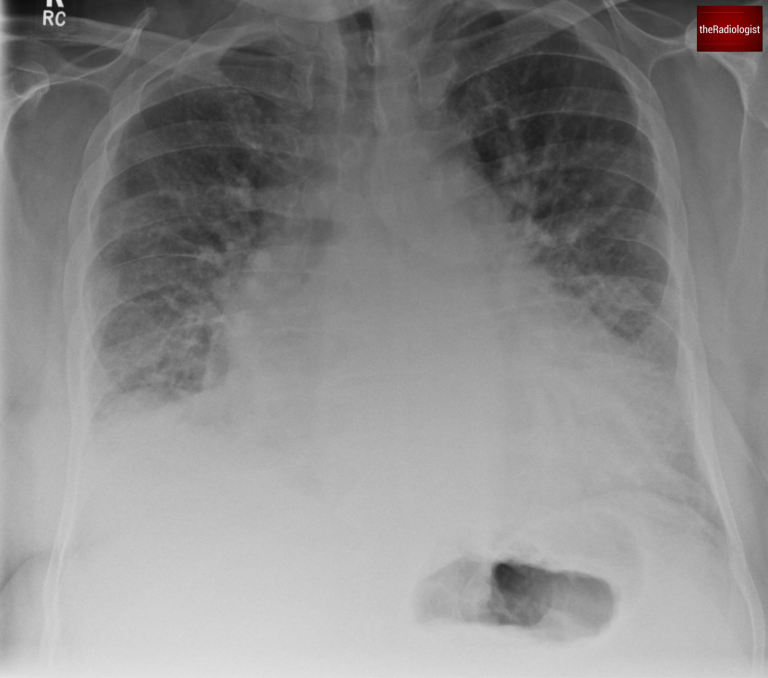

A 70-year-old male presents with breathlessness: have a look at his PA chest X-Ray. Let’s go through the case and have a think about pulmonary oedema.

PA view of a chest X-Ray of a male in his 70s

In this patient, the findings are consistent with cardiogenic pulmonary oedema, caused by left ventricular dysfunction secondary to ischaemic heart disease.

We see vascular redistribution, interstitial oedema, and alveolar oedema on the X-ray.